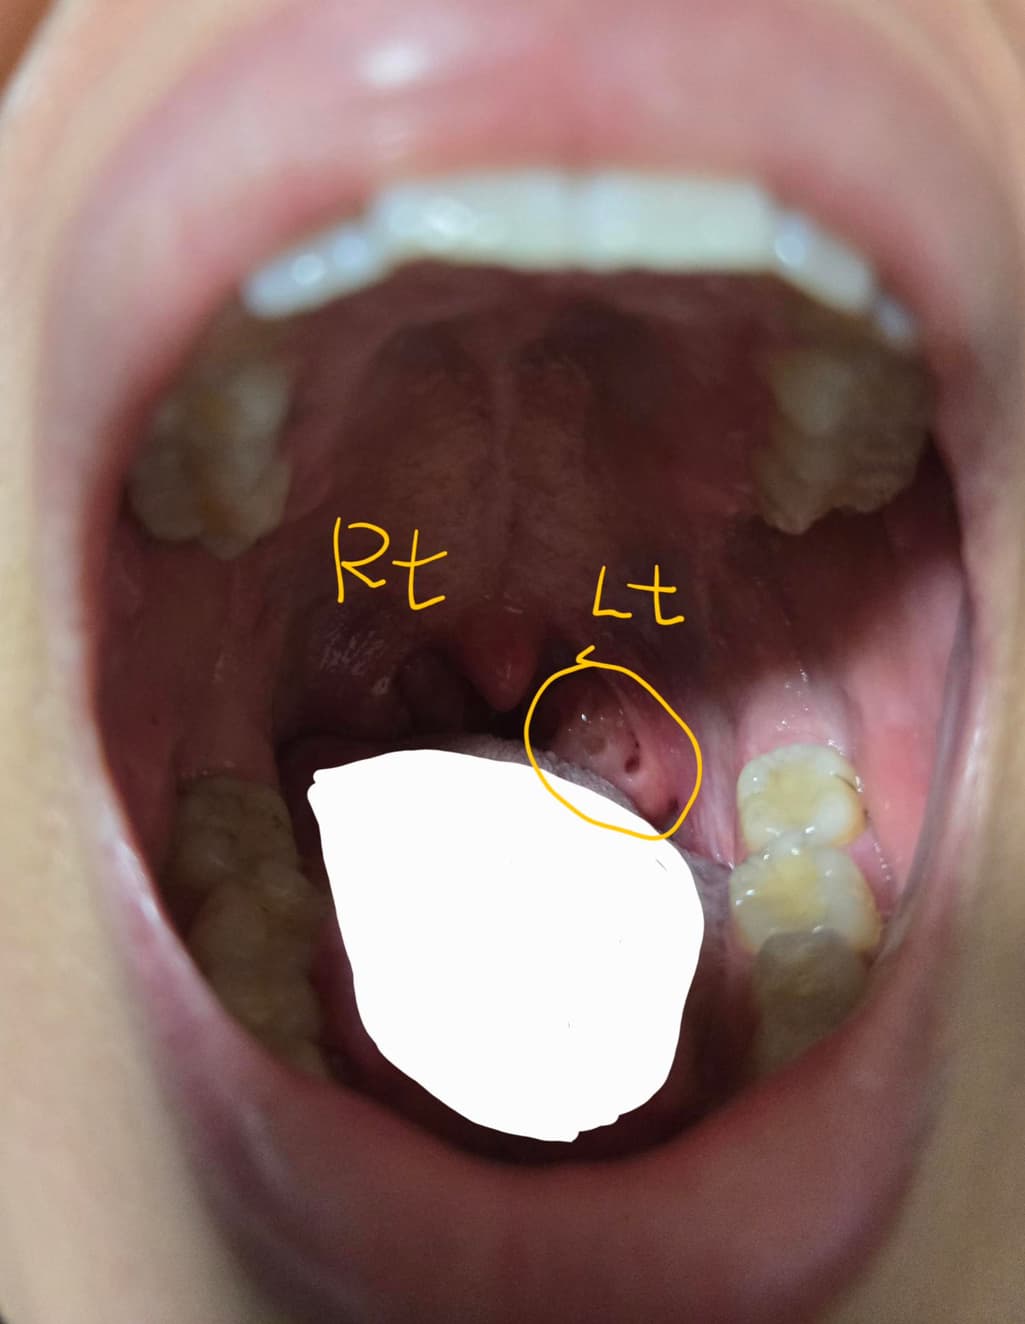

현재 사진에서는 왼쪽 편도에 구멍이 있는 것으로 보입니다. 보통, 편도 소립이라고 불리우는 구멍인데 해부학적으로 구조가 달라서 한쪽에만 결석이 생기는 경우가 간혹 발생하기도 합니다. (따라서 원래 한쪽만 그렇다고 보기는 어렵습니다.)

결석은 가글로 제거를 할 수 있지만, 구멍 자체를 없애는 것은 한계가 잇습니다. 비수술적인 방법은 대체적으로 결석을 없애는 데에 도움이 되고 구멍 자체를 메꾸는 방법은 현재로서는 없어 보입니다. 완전한 치료를 위해서는 편도 절제술과 같은 수술적 접근이 필요할 것으로 보이며 다만 일상 생활에서의 증상에 따라 치료 방법은 달라질 수 있어서 이비인후과에 다시 방문하셔서 정확한 치료 계획을 상의해 보시는 것이 좋을 것으로 사료됩니다.